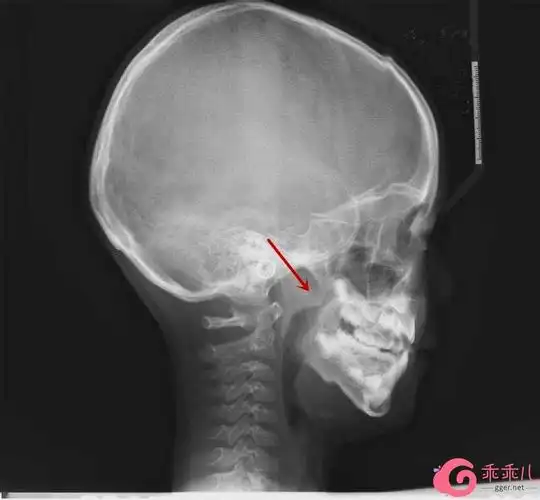

有些家长担心鼻咽侧位x光片辐射量较大,会对孩子身体造成损害.